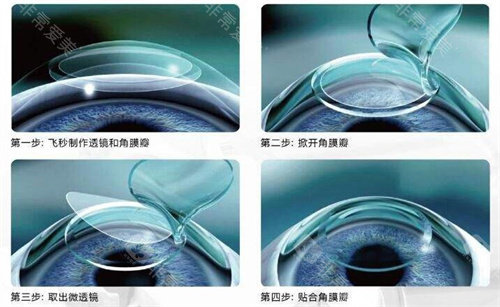

作为国内外规模比较靠前的眼科连锁机构,爱尔眼科在角膜交联领域优先实现三大技术升级:

飞秒激光辅助移植吻合精度达0.01毫米

中期病例:交联术联合板层移植,术后视力提升明显

晚期患者:穿透性移植联合生物工程角膜,降低排斥风险

术中:使用龙晶PR人工晶体(国产初款睫状沟固定型晶体)增强角膜稳定性